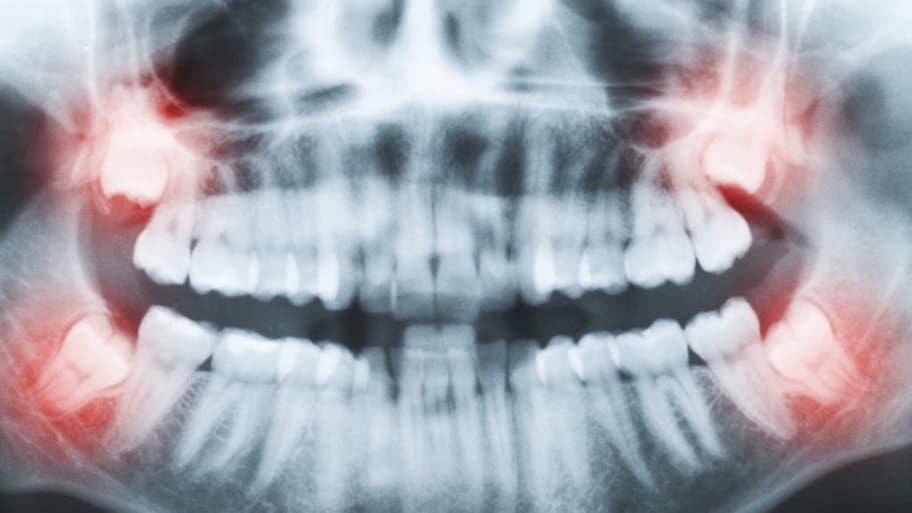

Vào ngày 15/7, một người phụ nữ họ Liao, 42 tuổi, ở bang Kedah, Malaysia, đã đến bệnh viện công để thực hiện tiểu phẫu loại bỏ răng khôn.

Theo China Press, chồng của cô cho hay, sau khi nhổ răng ở viện về, vết thương của cô vẫn tiếp tục chảy máu.

Cho đến tận sáng hôm sau, chiếc gối của cô Liao đã thấm đầy máu chảy ra từ trong miệng. Liao liền đến một phòng khám gần đó để tìm sự giúp đỡ, sau khi uống thuốc, hố răng đã bớt chảy máu.

Dù tình trạng chảy máu đã thuyên giảm, một số vết bầm tím lại xuất hiện dưới chân Liao. Đến ngày hôm sau, cô bị đau đầu và nôn ra dịch màu tối.

Gia đình Liao nhanh chóng đưa cô đến bệnh viện để cấp cứu. Tuy nhiên, cô đã rơi vào tình trạng hôn mê vào chiều hôm đó và qua đời vào ngày 21/7.

Bệnh viện cho hay, nguyên nhân khiến Liao tử vong là do u tuyến ức ác tính (hay còn gọi là thymoma) và chảy máu nội mô. Tuy nhiên, gia đình cô rất sốc và không tin vào nguyên nhân mà bệnh viện đưa ra.

Gia đình Liao không thể hiểu vì sao ung thư lại được cho là nguyên nhân gây tử vong, đặc biệt, cô đã chiến thắng u tuyến ức ác tính vào năm 2017 sau khi trải qua hóa trị.

Hiện tại, gia đình Liao đang cáo buộc sơ suất y tế khi nhổ răng khôn đã khiến cô qua đời.

Răng số 8 - răng khôn mọc... dại: Khi nào cần nhổ, nhổ có nguy hiểm không?

"Trước khi nhổ răng, tôi đã nhiều lần hỏi bác sĩ rằng, tiểu sử bệnh lý của cô ấy có ảnh hưởng gì không", chồng Liao nói.

"Họ nói rằng đó không phải là vấn đề - chỉ là cô ấy sẽ mất nhiều thời gian hơn để hồi phục."

Chồng Liao cũng đặt ra câu hỏi về việc, liệu hố răng của cô có được khâu đúng cách sau khi răng khôn được lấy ra.

Hiện tại, gia đình của Liao vẫn đang tranh đấu cho người phụ nữ quá cố và hy vọng rằng, Bộ Y tế Malaysia sẽ sát sao với vụ việc. Theo A.O, một quan chức y tế của bang Kedah đã từ chối trả lời các câu hỏi của báo chí.